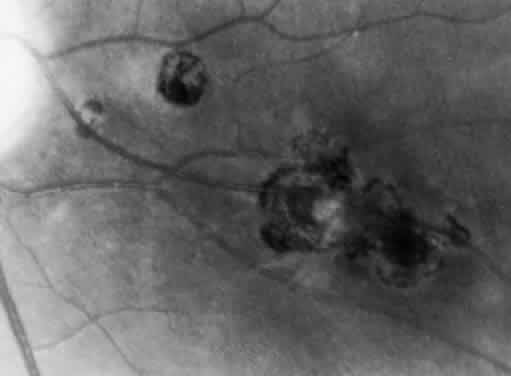

Ocular toxoplasmosis most commonly presents as a focus of necrotizing retinitis (Fig. 7) involving the inner layers of the retina and associated with a whitish fluffy lesion surrounded by retinal edema.6,59 Cells are seen in the vitreous overlying the lesion. The focus of retinitis may be large (Fig. 8) or small (Fig. 9). The retina is the primary site for the multiplying parasites, whereas the choroid and sclera may be the sites of contiguous inflammation. When the choroid is involved by the inflammatory reaction, the lesion is referred to as retinochoroiditis. The organisms are rarely seen in the choroid. The retinal lesion may be small and single or large and multiple and may reach several disc diameters in size. Large granulomas in the posterior segment of the eye frequently are seen in patients with ocular toxoplasmosis (Fig. 10). This is associated with extensive and marked vitreous reaction that precludes visualization of the retina, and the granuloma appears as a yellowish mass surrounded by a red reflex. Punctate outer retinal involvement may be seen in some patients with toxoplasmosis.60 These appear as multifocal, gray-white lesions in the deep retina and at the level of the retinal pigment epithelium accompanied by no overlying vitreous reactions. The lesions may resolve to form fine, granular white dots. This is the earliest finding seen in the rabbit models of ocular toxoplasmosis after the injection of Toxoplasma organisms in the suprachoroidal space. The lesions in the animal model may start as deep outer retinal punctate lesions that later involve the inner layers of the retina and cause the typical focus of retinochoroiditis. Involvement of the macular area is common in patients with congenital toxoplasmosis, and exudative retinal detachment may occur in severe cases. Clumps of inflammatory cells may be seen in the vitreous or over the detached posterior vitreous face. The focus of retinitis may be a manifestation of congenital toxoplasmosis or may be associated with or follow an episode of acquired systemic toxoplasmosis. Patients presenting with recurrent toxoplasmic retinochoroiditis usually are in the second or third decade, but the disorder may occur at any age. Healing of the retinitis is associated with a decrease in retinal edema and flattening of the lesion with evidence of scar formation surrounded by variable amounts of pigment (Fig. 11). The lesion may appear as a punchedout scar with underlying sclera resulting from extensive retinal and choroidal necrosis surrounded by pigment proliferation (Fig. 12), it may become a conglomerate or proliferated retinal pigment cells (Fig. 13), or it may be small and appear as a pigment clump in the retina. The retinochoroiditic scar may harbor the Toxoplasma cysts. Healing also is associated with decrease in the vitreous cells and improvement in visual acuity. Immunologic suppression is associated with recurrence of retinochoroiditis (Fig. 14). Recurrent toxoplasmic retinitis frequently appears as “satellites” or occurs adjacent to a previous scar. Old, inactive lesions often appear to be a conglomeration of previous multiple inflammatory foci (see Fig. 13).

Fig. 8. Severe Toxoplasma retinochoroiditis with large granuloma and overlying vitreous cells. A healed retinochoroiditic scar is seen in close proximity to the granuloma.

Fig. 9. A. A small focus of Toxoplasma retinochoroiditis adjacent to a healed retinochoroiditic scar near the equator in the right eye of a 23-year-old man. The Toxoplasma antibody titer IgG was 1:64 (indirect fluorescence antibody test). Such small lesions with minimal vitreous reaction may be observed and followed without treatment. B. Left eye of same patient showing a healed pigmented retinochoroiditic scar. Recurrences of Toxoplasma retinochoroiditis are not associated with an increase in antibody titer (B, Courtesy of Dr. John Cavender)